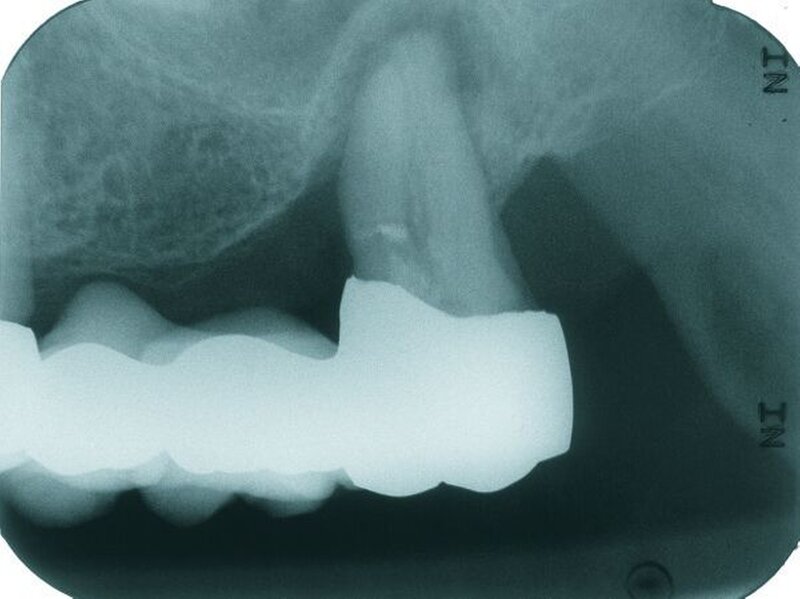

Röntgenbefund

Auf dem vor Anfertigung des Zahnersatzes angefertigten OPG sowie den angefertigten Zahnfilmen der regiones 17 und 27 waren generalisierte horizontale Knochenverluste im Bereich aller verbliebenen Zähne erkennbar. Die Zähne 17 und 27 wiesen zudem vertikale Knocheneinbrüche auf. Eine radiologische Furkationsbeteiligung ließ sich in beiden Fällen nachweisen. Der Zahn 47 war wurzelkanalgefüllt.

Obwohl der Zahn 47 eine radiologisch nicht vollständig bis zum radiologischen Apex reichende Wurzelfüllung aufwies, wurde auf eine Revision der Wurzelfüllung aufgrund einer seit mehr als 15 Jahren bestehenden Beschwerdefreiheit des Patienten und vollständiger Symptomlosigkeit des Zahnes verzichtet [Peak et al., 1994]. Der Patient wurde über diese Sachverhalte ausführlich aufgeklärt und erklärte sich mit dem Belassen der Wurzelfüllung einverstanden.